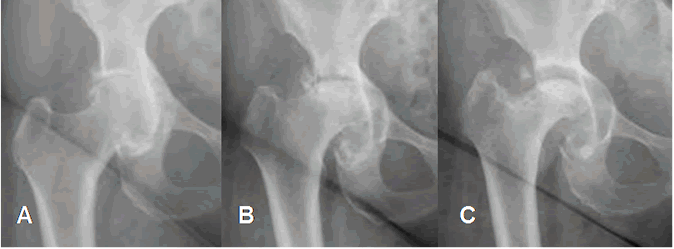

Fig 80. Artropatía rápidamente progresiva.

A: Rx AP. Signos de osteoartrosis.

B: 3 meses y C: 6 meses después. Progresión de los cambios degenerativos, con deformidad de la cabeza femoral y ensanchamiento de la cavidad acetabular.